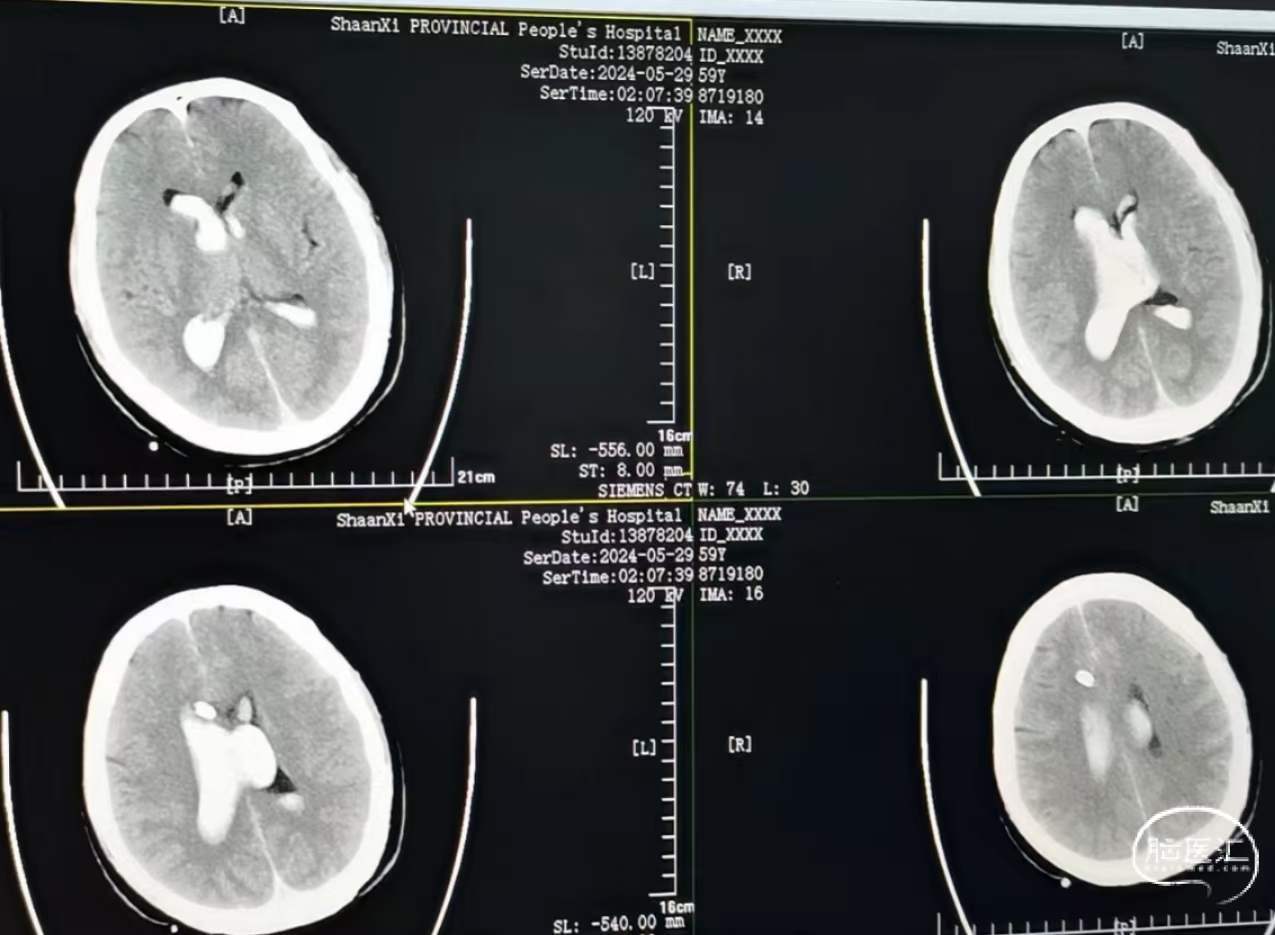

当地发现脑出血破入脑室,钻孔引流以后发现出血增加。查CTA发现有血管畸形,位于脑干旁边,有大脑后及脉络丛参与供血,急诊开颅,切除畸形并清除血肿。

畸形血管团,毗邻刚才所说的基底动脉、脑干、滑车神经、动眼神经,破裂出血。